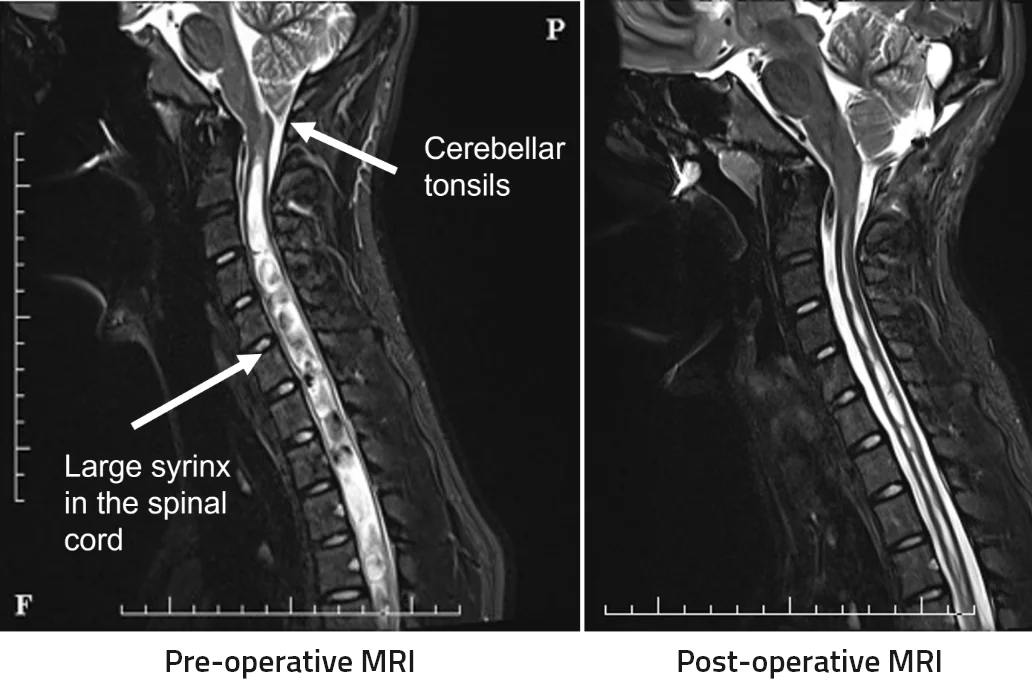

This young lady presented with an extensive spinal syrinx and a Chiari malformation.

She underwent a suboccipital craniotomy with duroplasty. Post-operative MRI at 3 months demonstrates that the Chiari malformation is well treated and her syrinx is dramatically reduced.